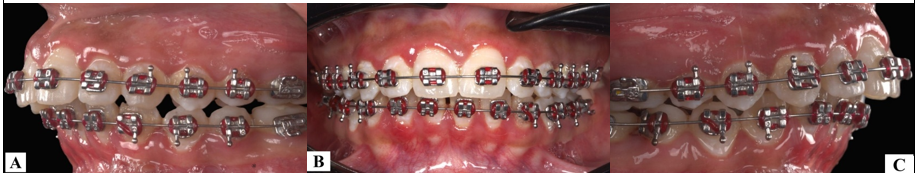

Association between Temporomandibular Joint Condylar Morphology and Habitual Chewing Side.

Mohammed Al-Maqaleh, Al-Kasem Abbas, Taghreed Al-Kibsi, Abdulbaset Mufadhal (Author)

434-441